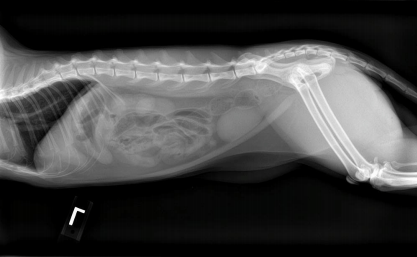

Digital radiography allows us to view your pet’s x-ray results within the blink of an eye! We can also send you and your primary veterinarian copies of these images for completeness of their medical history for your pet. In addition, when necessary we can access board-certified veterinary radiologists to use their specialized skill in interpreting your pet’s X-rays.